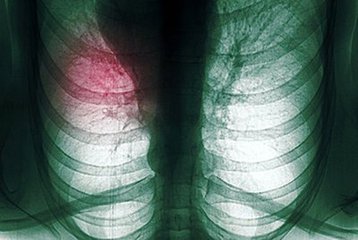

广州肺癌最好的医院专家的治疗原则?俗话说饭后一支烟赛过活神仙,但是大家知不知道其实吸烟对我们身体的伤害是非常严重的,特别是对我们肺部的伤害更是有过之而不足,特别是现在许多年轻人都有一个坏习惯,那就是吸烟,我们都知道吸烟有害健康,会给身体带来各种延伸得疾病,各种肺部疾病充斥在我们的周围。肺癌就是其中一种常见的肺部肿瘤疾病,首先我们来了解一些关于肺癌的治疗原则有哪些?

肺癌疾病的治疗可分为治疗原则

1.原发癌肿尚局限在肺内,尚未发生远处转移的病例,以外科手术治疗为主,术后可根据病理切片所见,辅以其他疗法是首选的治疗方案。